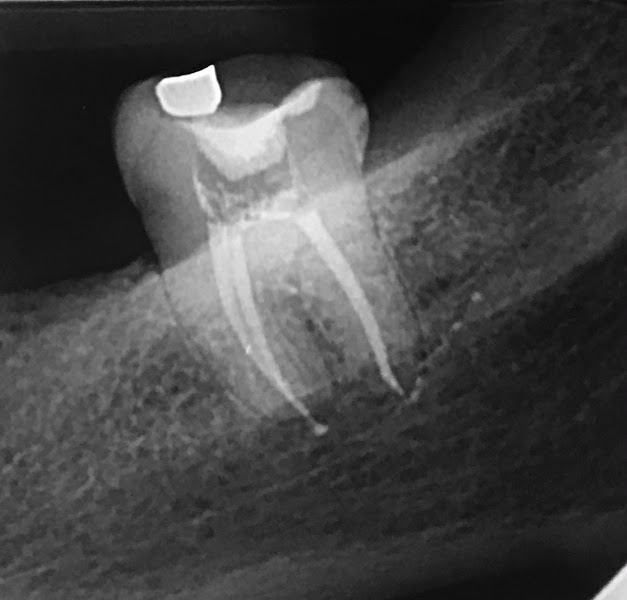

Dr.Matheus Nunes -Endodontista- Tratamento de Canal com Microscópio INFLORI CLÍNICA

“Quero registrar meus comentários do tratamento recebido nessa clínica com o Dr. Matheus, tanto em nível profissional, com esclarecimentos, instrumentação e equipamentos de última geração, ate o ser humano, respeitoso, gentil e extremamente educado. Desde o primeiro dia, com grande perda óssea e necessidade de retratamento de 4 canais, me senti segura e certa que o que pudesse ser feito para “salvar “ os dentes, seria feito. Preço justo e alem de tudo uma estrutura bacana e o atendimento totalmente personalizado, escutei o meu estilo musical em volume suave todas as vezes, como descrevi na pesquisa inicial que fizeram. Quero mais uma vez agradecer e indicar como uma das melhores experiências no resultado alcançado. Deus abençoe você Dr. ainda mais. Um exemplo a ser seguido. Quero acrescentar que lendo os comentários me lembrei, trabalho na zona sul e fui recomendada pelo meu cirurgião-dentista e confesso, a distância me desanimou até o primeiro contato, depois foi irrelevante. Parabéns!”